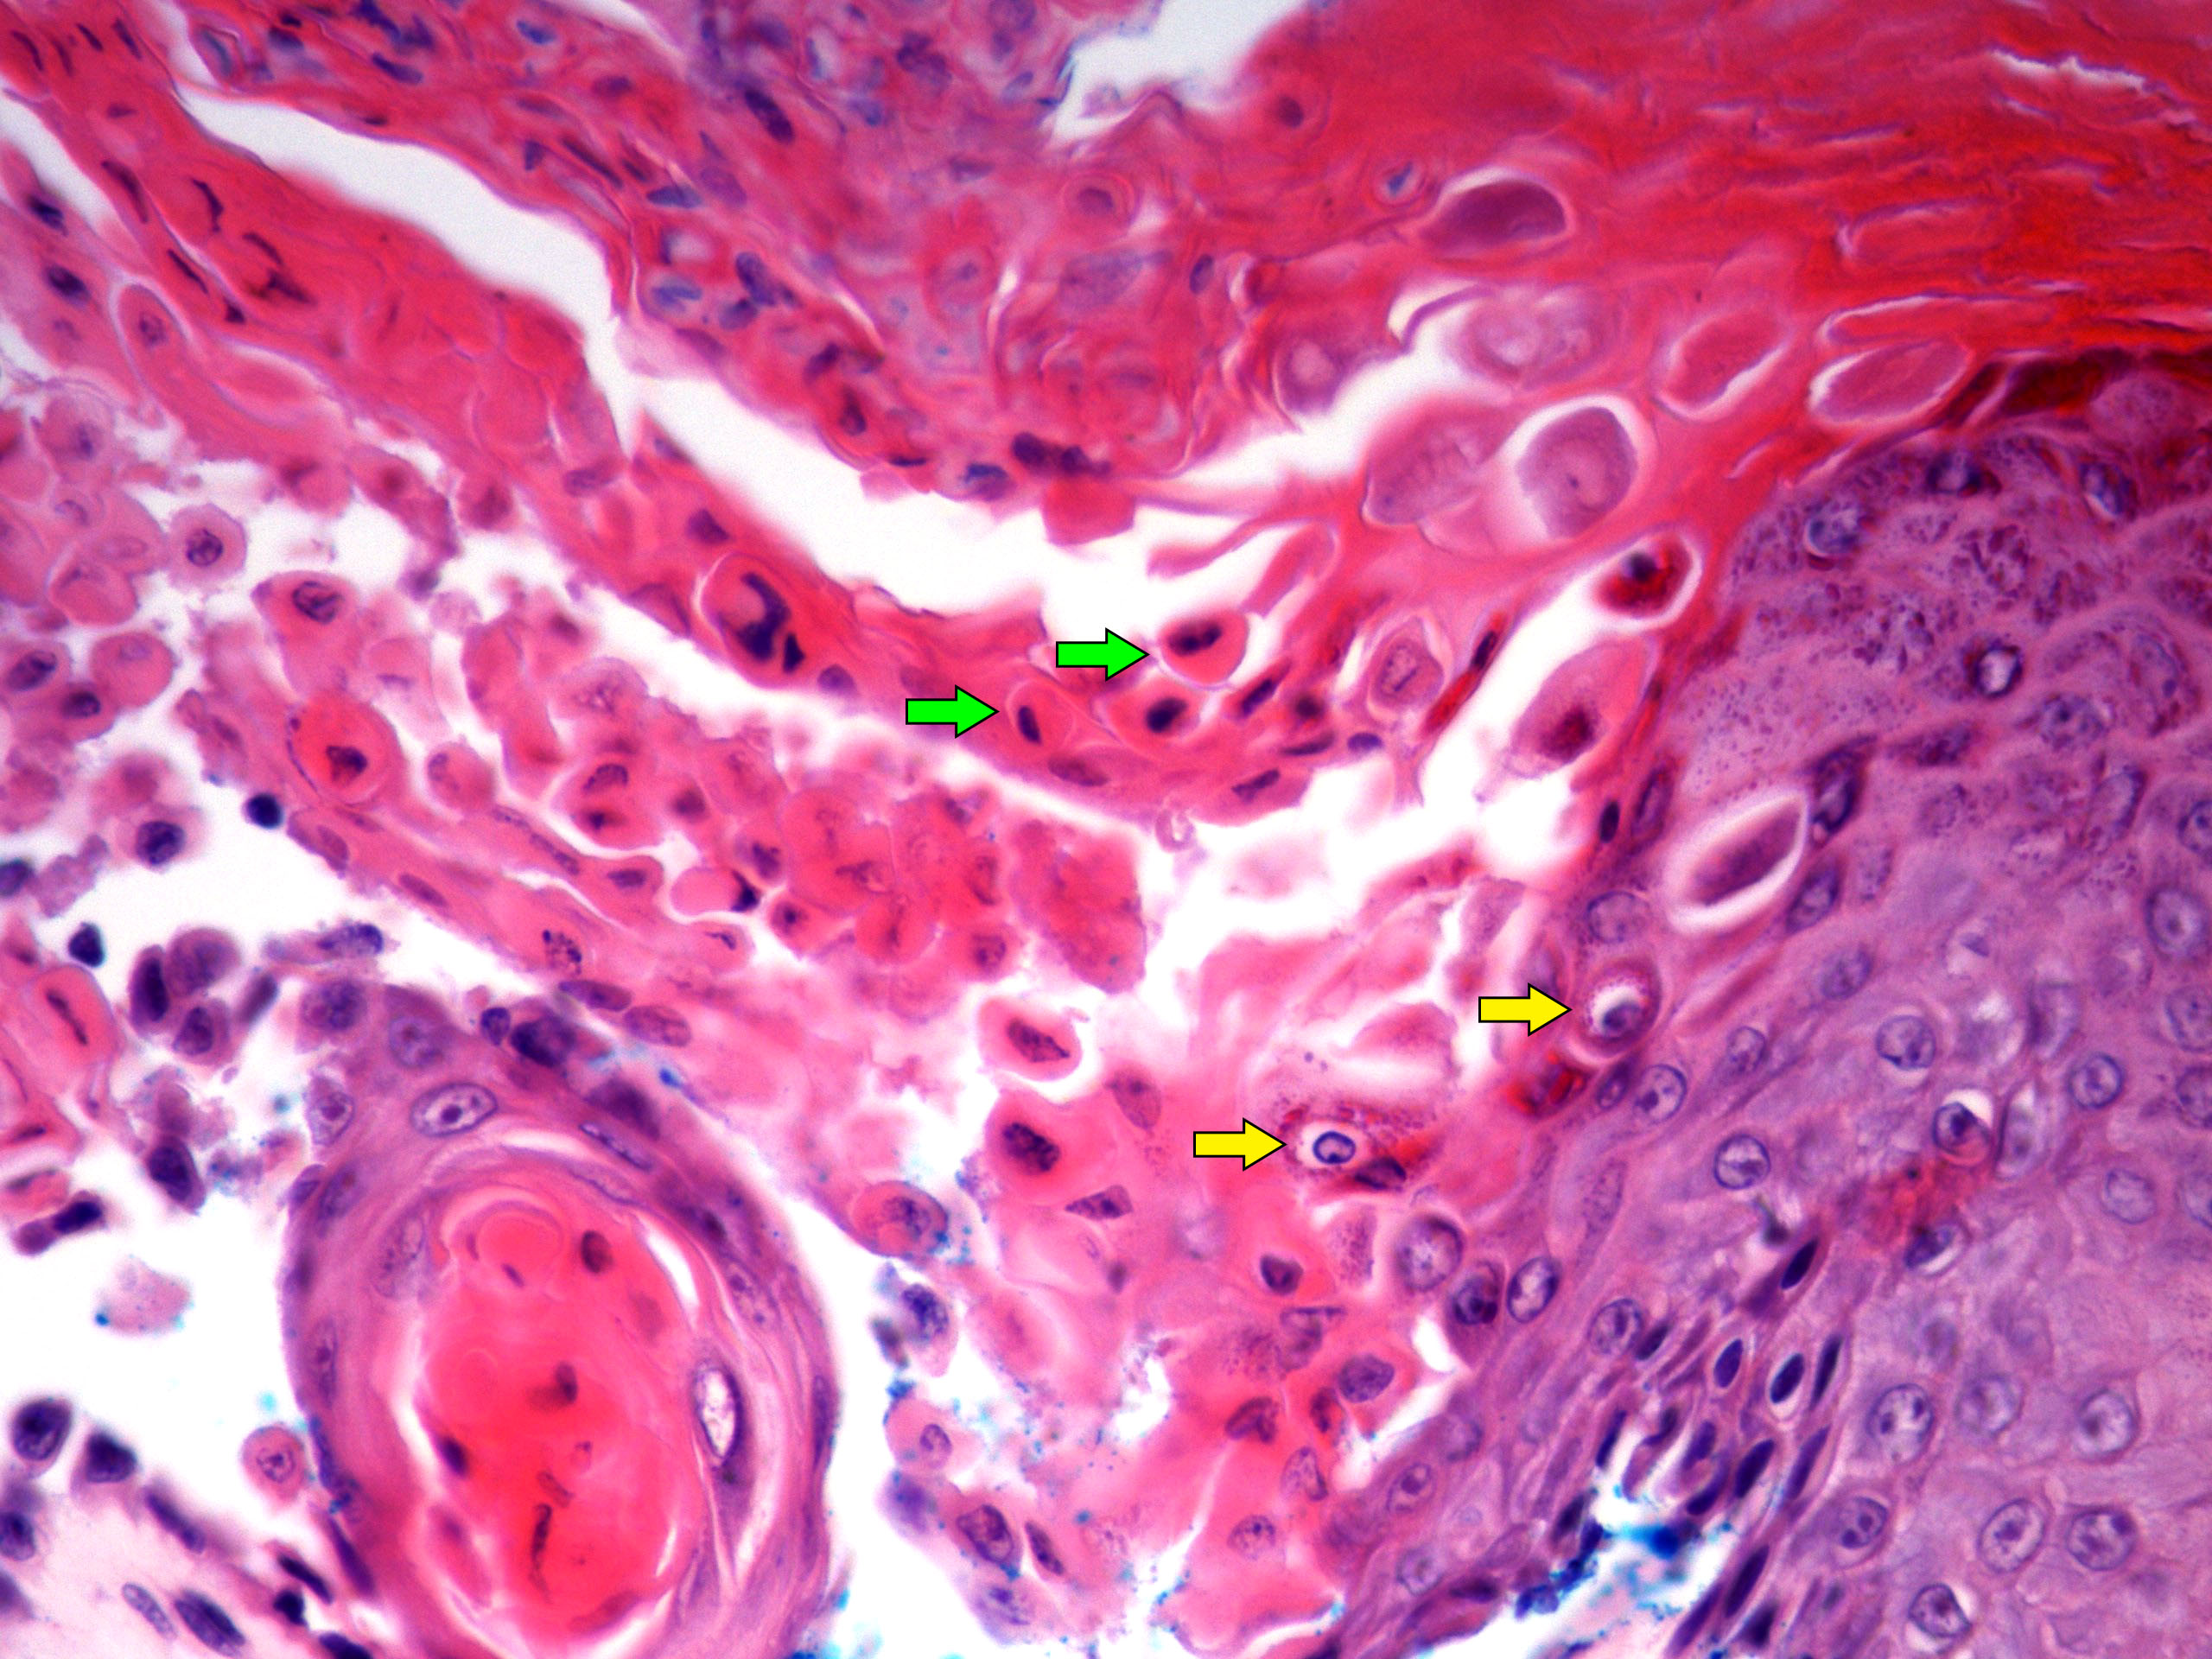

Microscopic (histologic) description

- Acantholysis with characteristic dyskeratosis forming corp ronds and grains

- Corp rond: rounded keratinocyte in superficial spiny and granular layer with basophilic / pyknotic nucleus, perinuclear halo and often a rim of eosinophilic cytoplasm (J Dermatol 2017;44:232)

- Grain: elongated keratinocyte in the stratum corneum with small basophilic nuclei and intensely pink cytoplasm; appears as plump parakeratosis; may form tiers (J Dermatol 2017;44:232)

- Suprabasal acantholysis and clefting with retained single layer of basal keratinocytes overlying dermal papillae which appear to project into the acantholytic cavity (villi) (J Dermatol 2016;43:275)

- Frank bullae may occur in cases with extensive acantholysis and large clefts (Arch Dermatol 1982;118:278)

Microscopic (histologic) images